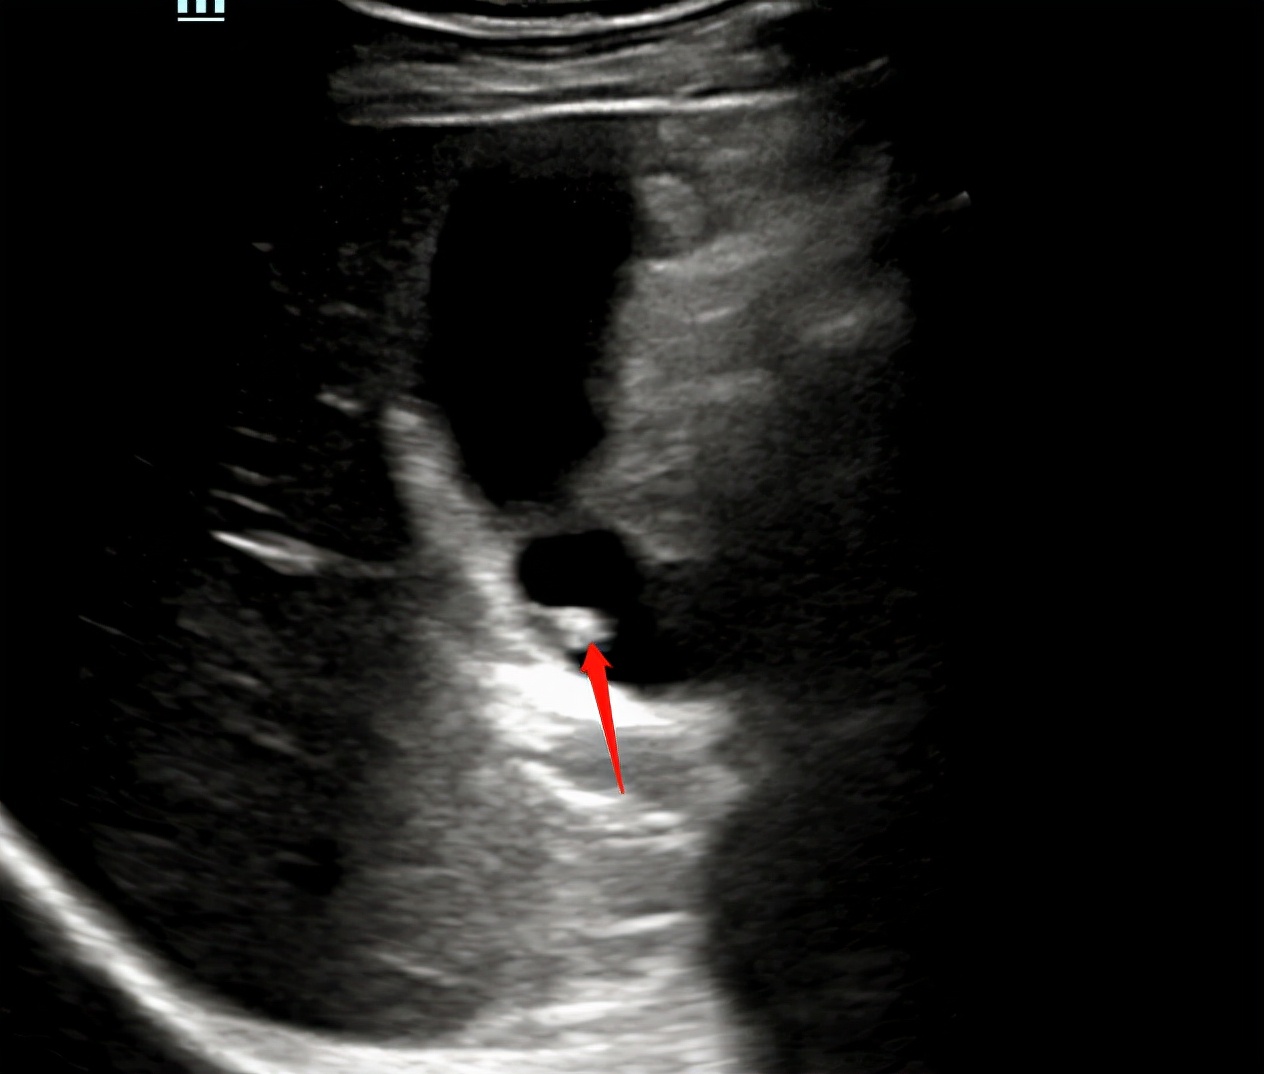

一边心想,一边让李四左侧卧位,从肋间看看胆囊

肋间明显看胆囊好点了,但胆囊颈部还是显示不清。。。。

那极有可能就是胆囊了,但是胆囊颈部有迷雾包绕,我已经换了好几个体位了,就连坐位都试过了,还是看不清。。。。

最终还是决定左侧卧位在肋间再仔细找找,因为这样看得更清楚些。

突然,在一个犄角旮旯发现个不明强回声。仿佛看到了黑暗中的黎明。。。

疑似啊,疑似,还不能确诊,咋整呢?????